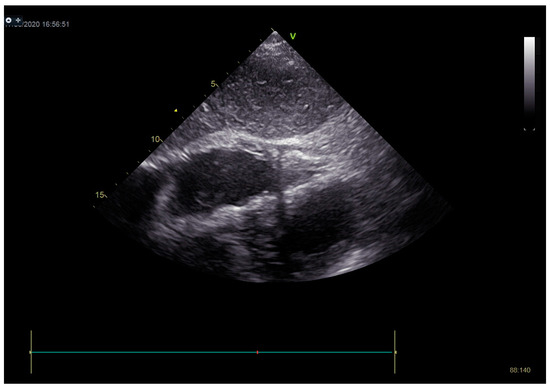

In the following course of treatment, the patient became hemodynamically unstable, despite high doses of inotropes and vasopressors. Echocardiography registered a more significant amount of effusion around the heart compared to the previous exam, with signs of cardiac tamponade (Figure 9). Pericardiocentesis was performed, and 260 mL of hemorrhagic fluid was drained (Figure 10).

Figure 9.

Echocardiography registered a larger amount of effusion around the heart compared to the first exam, with signs of cardiac tamponade.

Figure 10.

On echocardiography after pericardiocentesis, pericardial effusion was not registered.